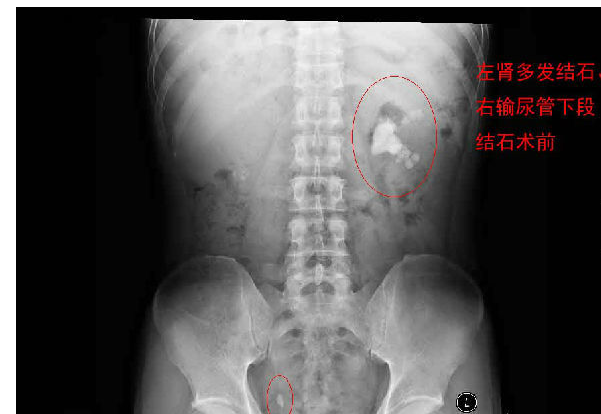

每天早上手术间响起泌外医生们特有的交谈声音和机器们互相的运转声交替成了一道熟悉不变的旋律,从手术室护士摆着各种专用体位,推着各种器械,液体进进出出,医生们应用着各种碎石手段消灭石头,利用气压弹道、激光、超声等碎石工具,把结石击碎取出,一阵忙碌的节奏。泌尿外科的手术时间都不长,每天手术例数又多,你就会看见这么一群人来来回回,医生护士还是那么个,病人都换了无数。最长一次从早上8点到隔天凌晨2点才结束手术,回到家就立马睡觉都顾不上吃饭。现在手术间正做着一台经皮肾镜下碎石取石术,这是我们医院泌外科的王牌。

经皮肾镜取石术,就是在腰部建立一条从皮肤到肾脏的通道,通过这个通道把肾镜插入肾脏,英文简写为PCNL。经皮肾镜取石术是肾结石治疗的现代微创技术,我院在惠州率先开展此项技术,现在每年进行数百例手术,基本上已经淘汰了开放手术取石。经皮肾镜取石术是一项技术性非常强的手术。我们知道,肾脏是血管非常丰富的器官,肾脏血流占心脏排出血量的1/4。既要尽量避免出血、又要努力取净结石、还要保护肾脏功能,这需要非常精细的手术技术。从某种程度上说,这个手术要比治疗肾癌的肾切除术难度大很多。传统的“开刀取石”的方法,需要在腰部做一个的大切口,切开腰部的肌肉,把肾脏分离出来,在肾盂或肾实质切开一个小口,将结石取出来。这种方法损伤大、出血较多、痛苦重、恢复慢。通常手术后需要住院7天以上。因为手术切口大,不但皮肤不美观,而且手术后患者的体力受影响比较大。与开放手术相比,经皮肾镜取石术具有损伤小、痛苦轻、取石彻底、恢复快等优点。腰部的切口通常小,因为不切开肌肉,不但不影响美观,而且手术后对劳动力几乎没有影响。手术后住院时间也明显缩短。与腹腔镜取石相比,经皮肾镜取石术对肾脏及周围的结构影响小,不影响以后的各种肾脏手术。与体外碎石相比,它的治疗周期短、效果立竿见影,对肾功能的影响也较小。(手术室/麻醉科 阮伊莎)